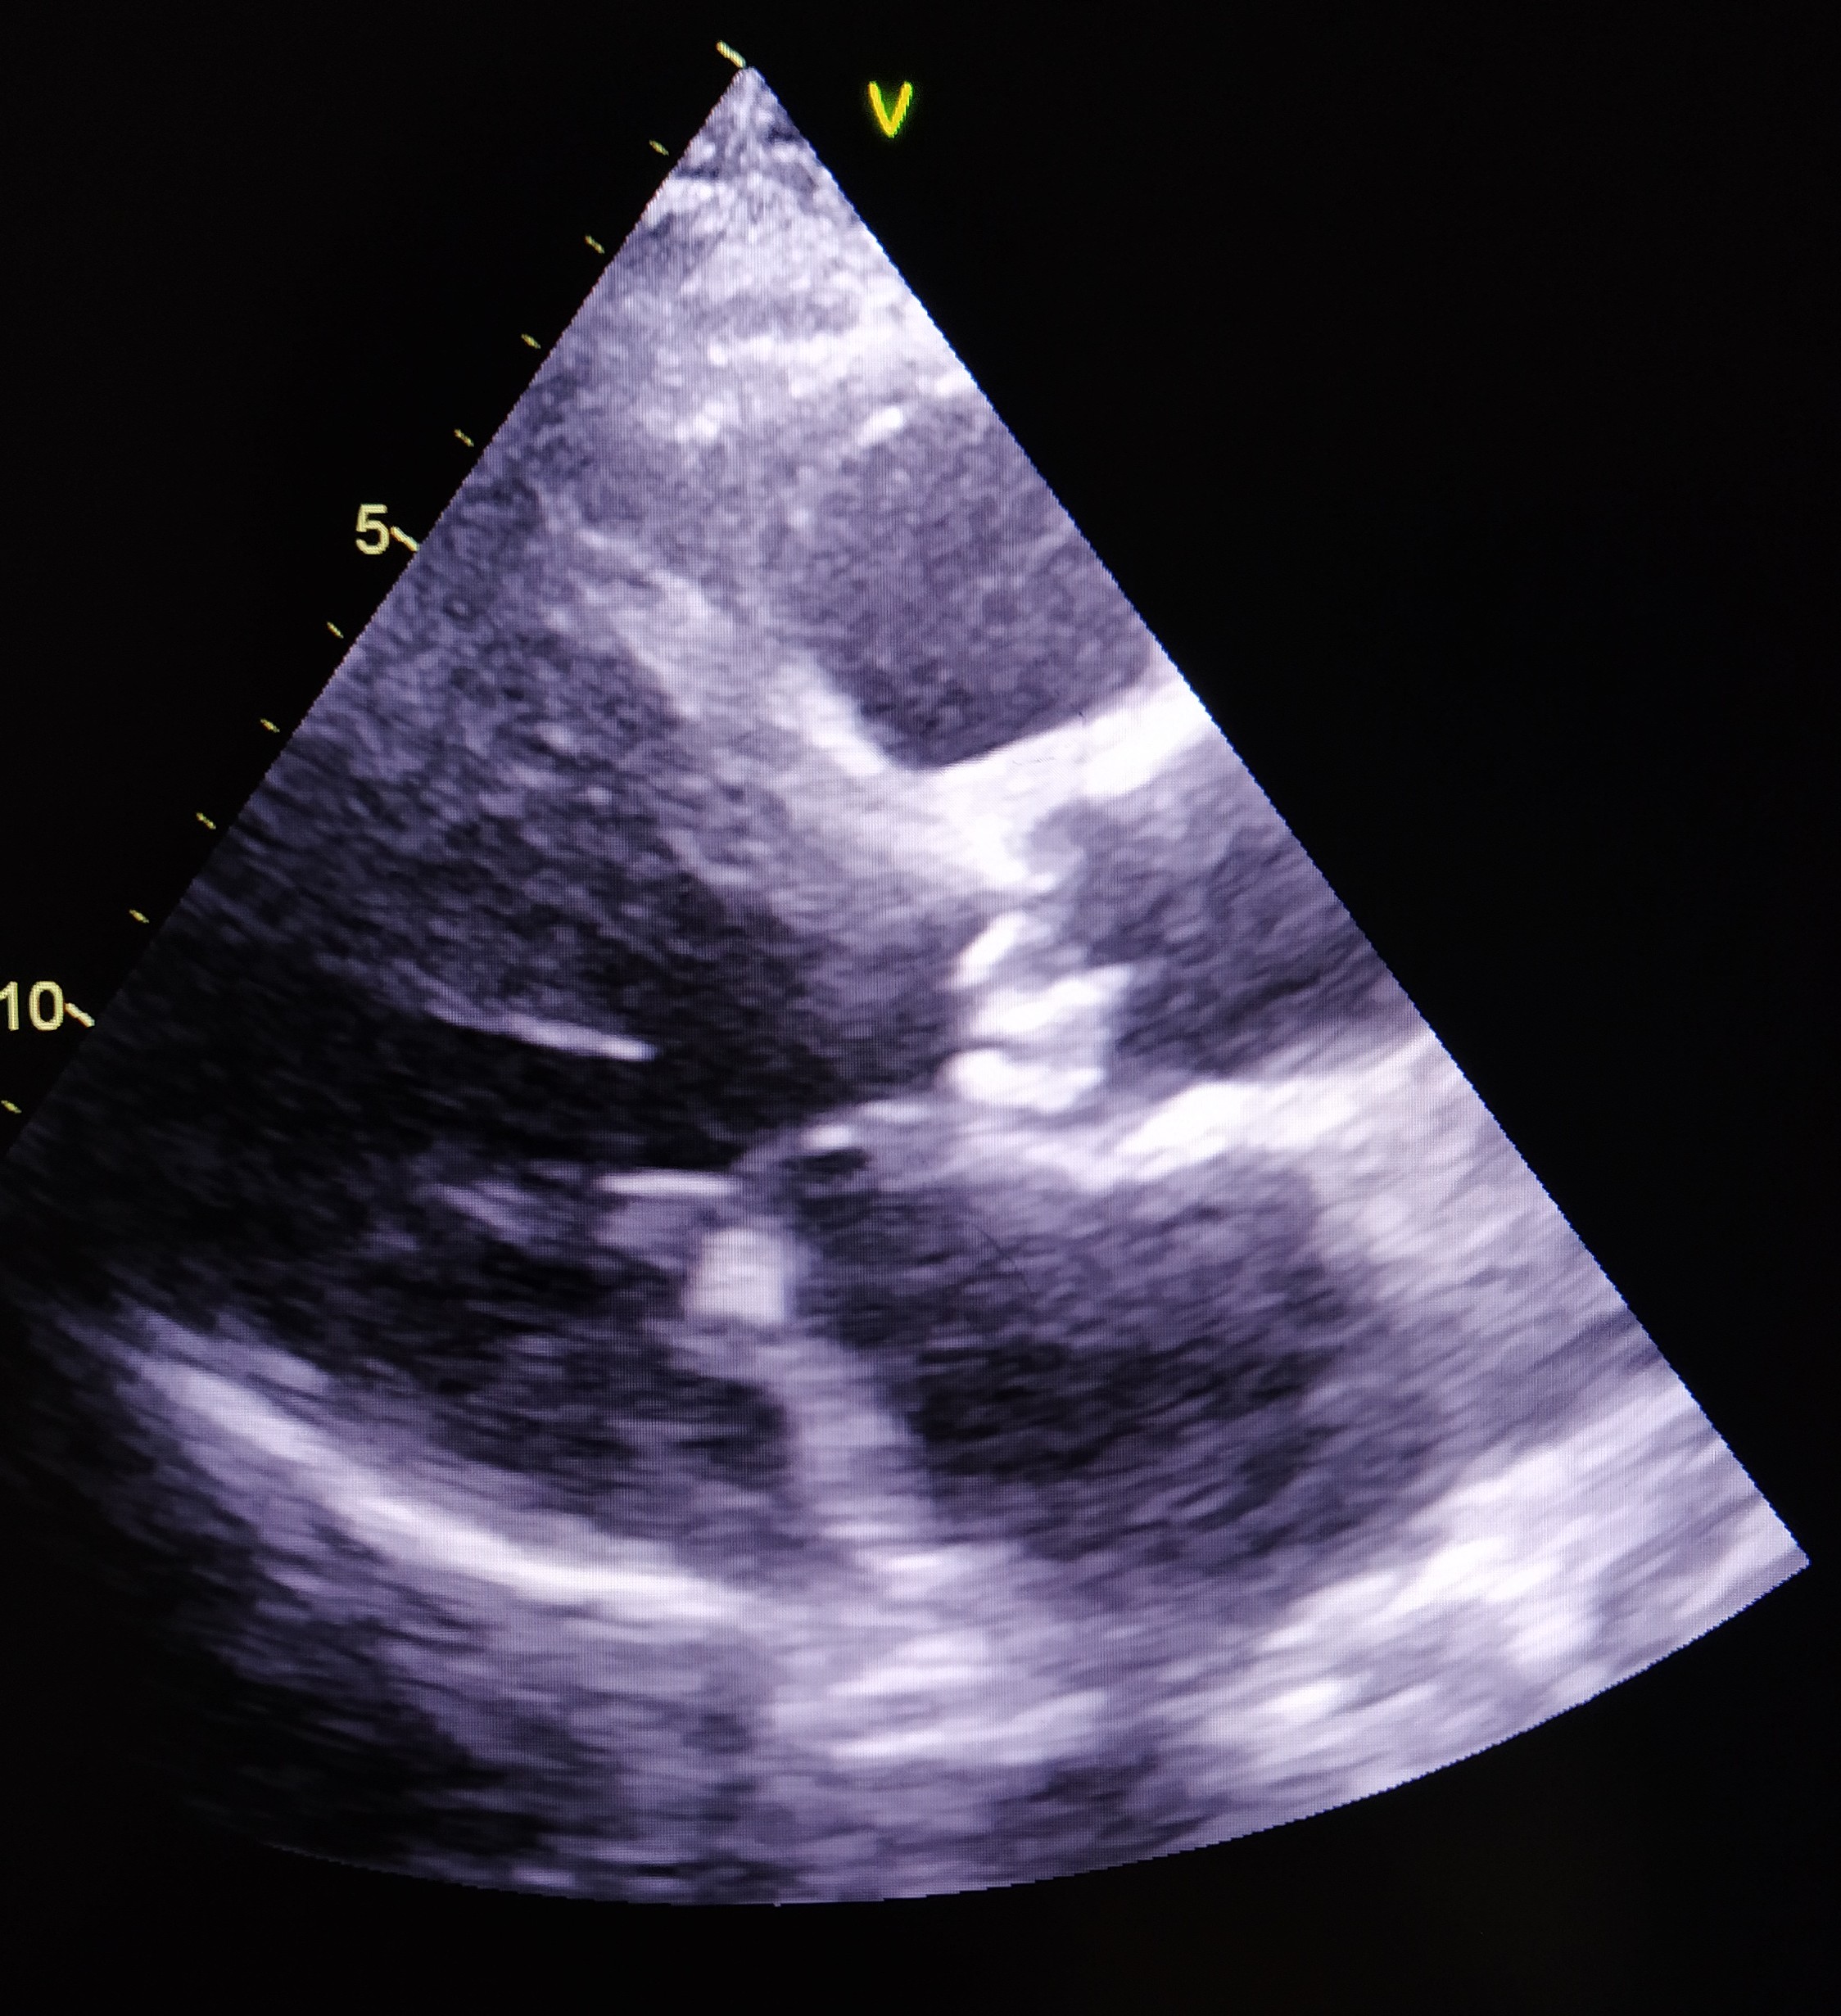

Resim 2. Tedavi Sonrası Yapılan Transözofageal Ekokardiyografide (TÖE) Vejetatif Lezyon Saptanmayan Görüntü

Tedavinin 42. gününde TÖE’de vejetasyonun kaybolduğu saptandı (Tablo 2, Resim 2). Bunun üzerine TMP-SMX 6 haftaya, levofloksasin ise 5 haftaya tamamlanarak kesildi. Elektrolit dengesi düzelen hasta yatışının 53. gününde şifa ile taburcu edildi.